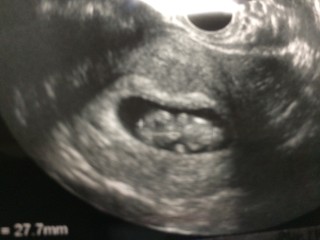

最終生理から10w6dでしたが、今日の検診で9w6dに確定しました! エコー見てた時に、ものすごく体を動かしていて感動しました!! この時期も体たくさん動かすんですね! 2週間前は14mmだったのが、27.5mmになりました! 元気いっぱいで一安心。 これから順調に育つことを願います。